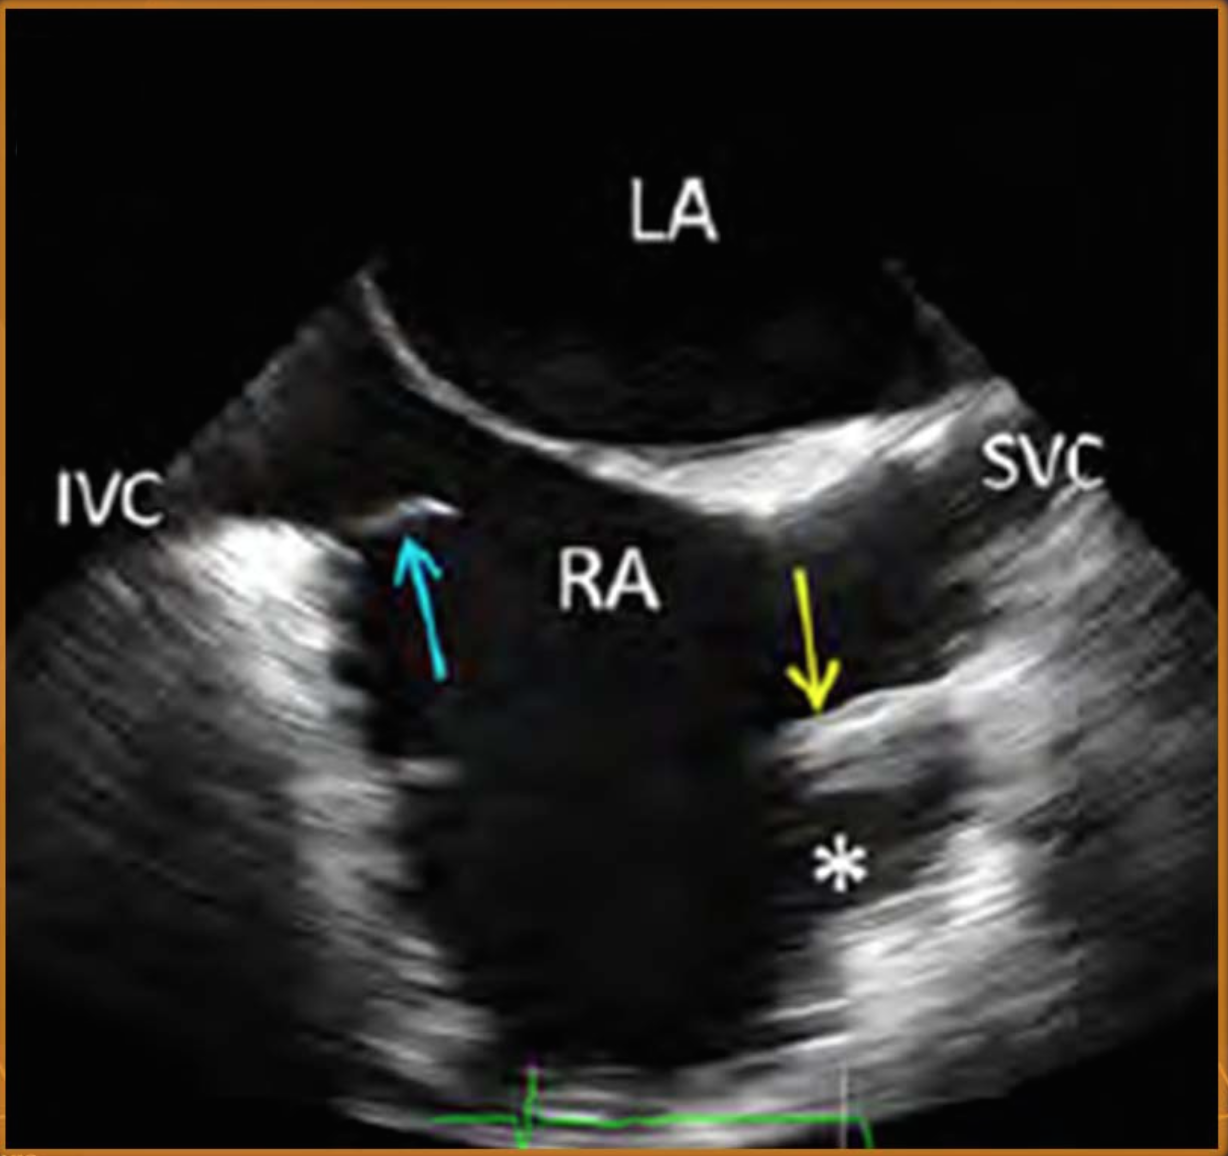

what are arrows pointing to?

blue = eustachian valve (large = chiari network), yellow = crista terminalis